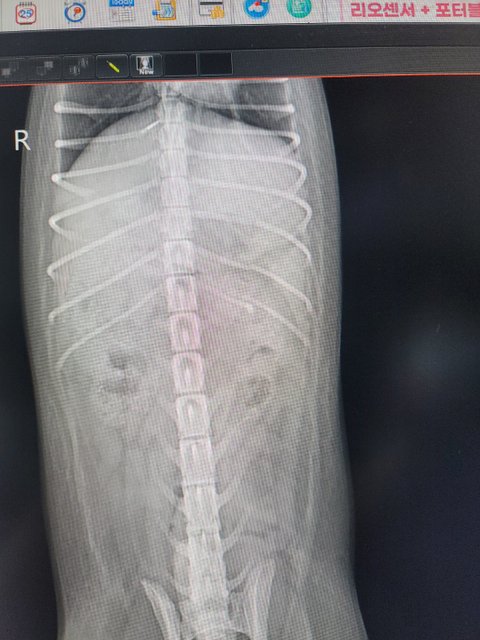

다행히도 집 근처 24시 동물병원이 있어 급하게 병원에 데려가서 이것 저것 검사를 했더니, 갈비늑골 3개가 부러져있고, 두개골 파열에 복부 멍자국, 신경계 이상등..단 5일사이에 강아지가 이상해져서 돌아왔습니다.

검사 결과 두개골 골절로 인한 뇌출혈 및 우뇌 이상 소견 받았습니다.